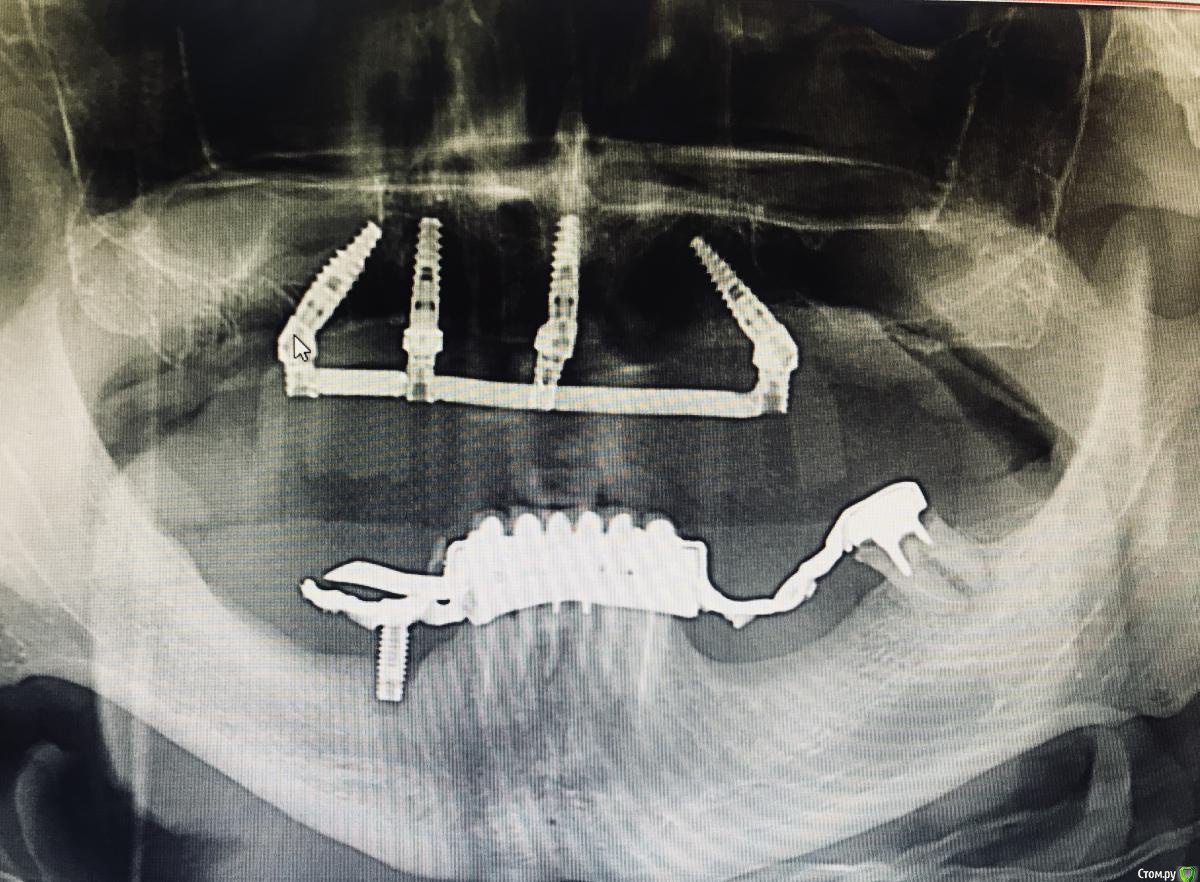

DoctorT Опубликовано 14 июля, 2018 Поделиться Опубликовано 14 июля, 2018 (изменено) От и до ровно сутки. Н/ч на очереди. Изменено 14 июля, 2018 пользователем DoctorT Ссылка на комментарий

zubovolok Опубликовано 16 июля, 2018 Поделиться Опубликовано 16 июля, 2018 От и до ровно сутки. Н/ч на очереди.А внизу что за конструкция? Я так понимаю бюгель на атачменнах? Насколько скоро принесёт в руках имплант и лкв с коронкой с 3.7?) Ссылка на комментарий

Evgen-Vozhd Опубликовано 19 июля, 2018 Поделиться Опубликовано 19 июля, 2018 Можно подробнее?ПРикручиваем абатменты и регистрация прикуса с их уро Вот что получается в итоге Ссылка на комментарий